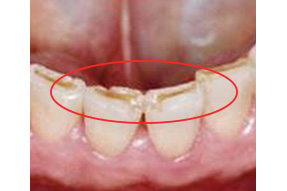

アブフラクション(くさび状欠損)

歯の根元(歯頸部)に応力が集中し、エナメル質が微細に亀裂・剥離して、くさび状に欠けてきます。